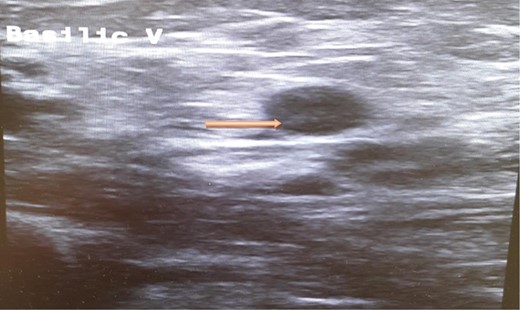

A computed tomography scan of the chest, abdomen and pelvis revealed splenic vein thrombosis (Fig. 1); and a filling defect in the lower lobar segmental branch of the right pulmonary artery consistent with acute segmental pulmonary embolism. A venous duplex scan of the extremities showed thrombosis of the left axillary and basilic veins (Figs 2 and 3). Echocardiogram was normal.

Ultrasound scan of the axillary vein with evidence of thrombus formation.